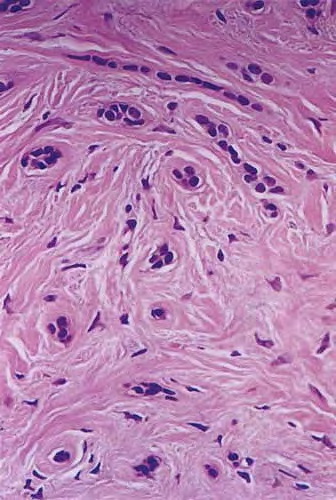

MICROCYSTIC ADNEXAL

CARCINOMA

MAC is also known as syringomatous carcinoma and sclerosing sweat duct carcinoma.

MAC is a rare, locally aggressive tumor with a high potential for local recurrence.

Local recurrences are common (about 50 percent of cases) and may develop several years after initial diagnosis and therapy. Prolonged follow-up is therefore usually necessary.

Treatment of choice is surgical. A more favorable cure rate (up to 89 percent) has been achieved with Mohs micrographic surgery. Regional and distant metastases are rare